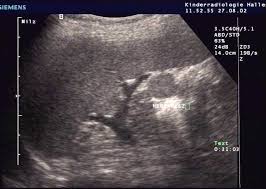

Junctional Parenchymal Defect Kidney Ultrasound. The intermediate septum is a band like cortex running obliquely in the central echo complex. Thirty such cases arepresented.

Thirty such cases arepresented. Some authors have suggested that these structures result f. Carter ar horgan jg jennings ta rosenfield at.

Triangular echogenic area in the anterior aspect of the kidney. Carter ar horgan jg jennings ta rosenfield at. Junctional parenchymal defect jpd is a triangular or linear hyperechoic structure in the anterosuperior or posteroinferior surface of the kidney. A triangular echogenic area in the upper pole renal parenchyma can be identified at times during routine sonography of the right kidney.